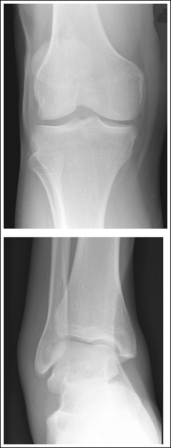

The lower leg demonstrates an AP projection. The tibia demonstrates only minimal superimposition of the proximal and distal fibula, and the fibular midshaft is demonstrated free of tibial superimposition.

The knee and tibiotalar joint spaces are closed.

• The proximal tibia slopes distally from the anterior condylar margin to the posterior condylar margin by approximately 5 degrees. When the lower leg is placed parallel with the IR and the central ray is centered to the midshaft of the lower leg, x-rays that diverge in the opposite direction are used to record the image of the proximal tibia (see Figure 6-66). The distal lower leg also slopes distally from the anterior tibial margin to the posterior margin by approximately 3 degrees. Although the x-rays diverge in the same direction as the slope of the distal tibia, they diverge at a greater angle. Because the angle of x-ray divergence is not aligned parallel with either the proximal or distal tibia, the knee and ankle joints are demonstrated as closed spaces on an AP lower leg projection.

The tibial midshaft is at the center of the exposure field. The tibia, fibula, ankle, knee, and surrounding lower leg soft tissue are included within the collimated field.

• A perpendicular central ray is centered to the midpoint of the lower leg to place it in the center of the image.

• To include the ankle and knee joints on the image, you must consider the degree of x-ray beam divergence that occurs when a long body part is imaged (Figure 6-66). A 14- × 17-inch (35- × 43-cm) detailed screen-film or computed radiography IR should be adequate to include both the ankle and knee. When a screen-film system is used, the leg can be positioned diagonally to accommodate the length. For the computed radiography system, it is not advisable to do this unless the system is set to handle this alignment. To ensure that both joints are included, the film should extend 1 to 1.5 inches (2.5 to 4 cm) beyond each joint space. The ankle is located at the level of the medial malleolus, and the knee joint is located 1 inch (2.5 cm) distal to the palpable medial epicondyle.